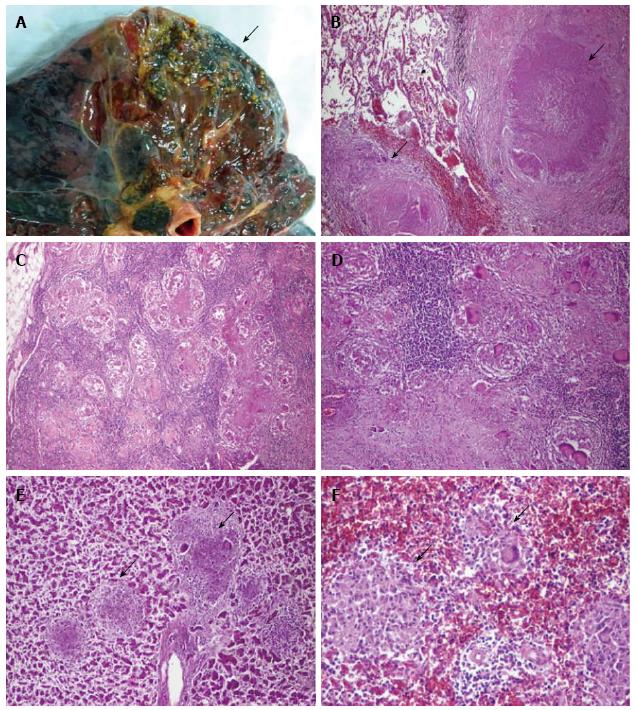

Микроскопический взгляд на мишитарный туберкулез легкого: фотодокументация

Раздел: Снимки-откровения